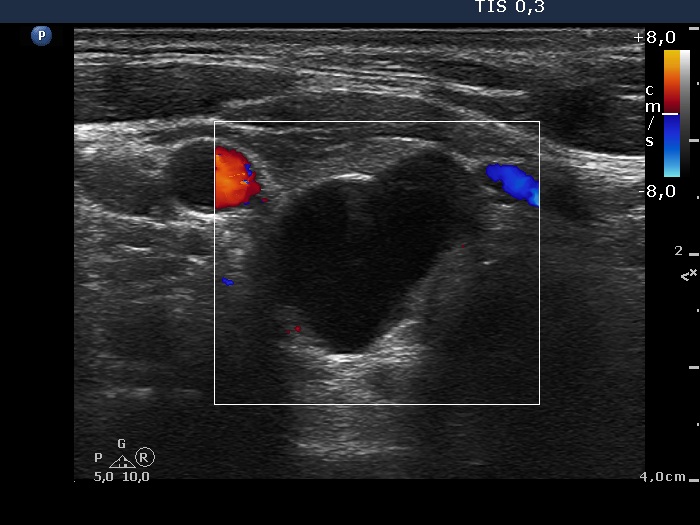

Ultrasonography: The thyroid was minimally-moderately hypoechogenic and presented fibrosis. There was a cystic lesion in the lower dorsal part of the right thyroid bed.

Twelve mL cystic fluid was aspirated. There were no cells on the smear.